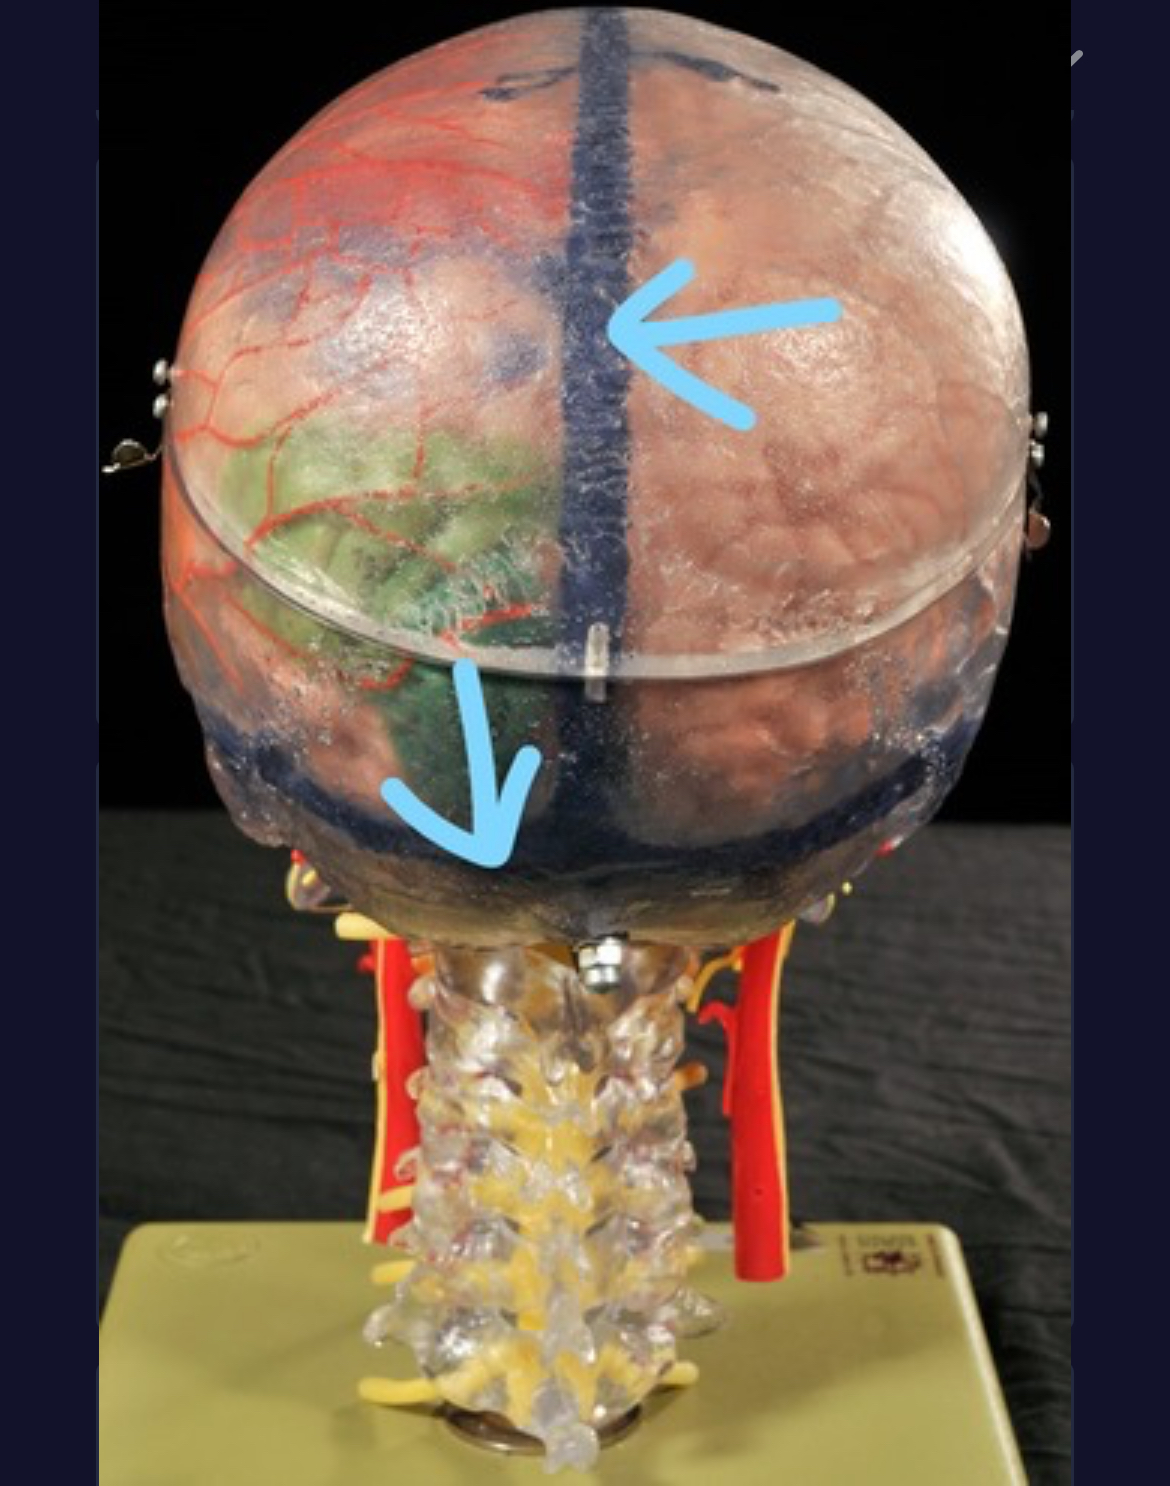

Longitudinal fissure

Cerebral cortex (gray matter)

Cerebral medulla (white matter)

Corpus callosum